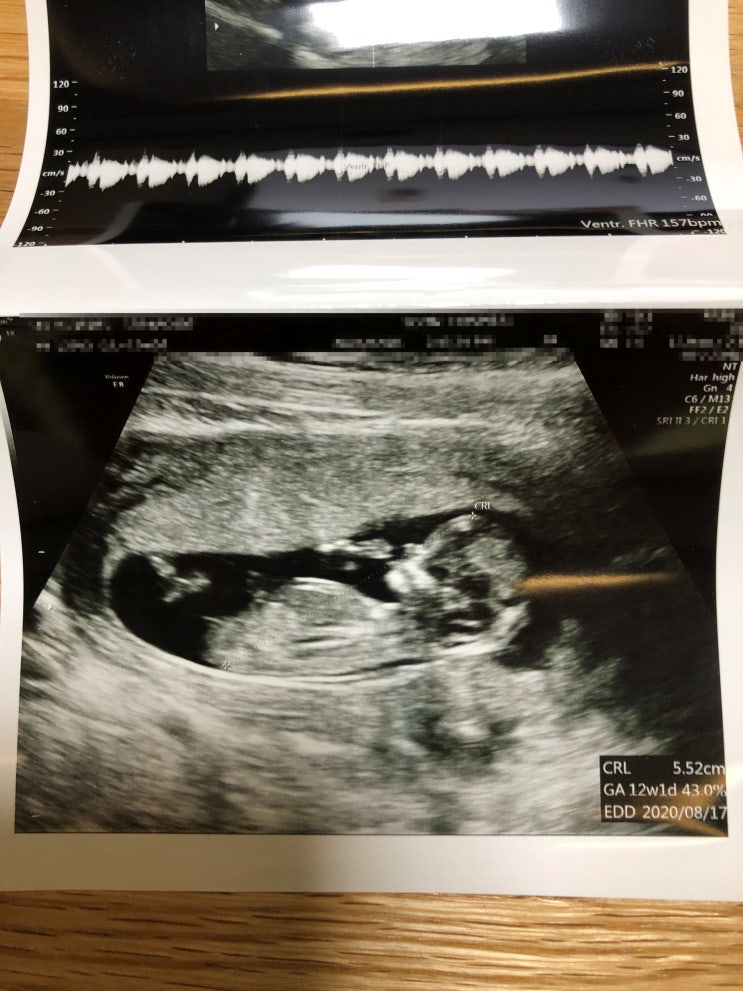

4번째 진료 기형아검사

3주 뒤 2월 4일 어제 1차 기형아 검사가 있는 날 초음파실에 따로 가서 먼저 애기 초음파부터 봤다 접수하...